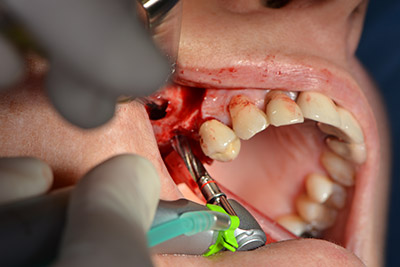

About six months after teeth 16 and 14 were extracted, a digital volume tomography (DVT, Planmeca) examination was performed for planning and risk minimization purposes. It clearly showed that the bone had not regenerated to the desired volume (Fig. 2 to 7).

Image 2 to 7: DVT with greatly reduced horizontal bone volume.

A sinus floor elevation was required in both regions 16 and 14 to guarantee a fixed restoration based on at least two implants. Relatively large-scale bone augmentation was required due to the residual bone volume being extremely low in this case. Major bone augmentation procedures are invasive and linked to higher patient morbidity, as well as being time-consuming and expensive. It is more difficult to predict the results of the treatment and the risk of failure is increased. The patient was informed of the increased risk and was offered a removable solution, which she consistently rejected.

To restrict the augmentation to region 14, and in consultation with the patient, it was planned that implant 16 would be placed, inclined, in the dorso-cranial direction (Fig. 8).